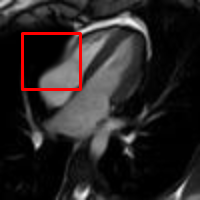

Example 2: The next example is on a sequence of real medical images of a beating heart. The original video contains 341 frames with repeated periodic beating of 31 times. In this example, artificial abnormal deformations are introduced to one of the 31 cycles, and so ground-truth images are available to study the accuracy of our proposed model. Table 2 shows the result. The second column shows the frames with manual deformation added on images in the first column, and the red box area is where deformation is added. We can see that our algorithm can almost recover the low-rank frames to the original frames and the sparse frames to the perturbed frames. The size of the input Beltrami descriptor is , and the rank of the original video and perturbed video are 11 and 15 respectively. After running our algorithm on the matrix, the rank of the recovered low-rank matrix is reduced to 11.

Beside the recovered rank, from Table 2, we can see that our algorithm can capture and recover both the normal and abnormal deformation on the beating heart to great details. It can be seen that the recovered low-rank frames looks very much alike to the original frames and recovered sparse frames can effective capture the abnormal deformation.

To better observe the result of our experiment, Figure 3 shows the second row of Table 2. The area bounded by the red box is the periphery of the beating heart. Figure 3(a) shows the ground truth frame. Figure 3(b) shows a frame with a perturbation combined with the normal deformation. The deformation between a frame and the reference image is computed by registration and represented by the Beltrami coefficient. Figure 3(c) shows the deformed image from the reference frame by the low rank part of the deformation. It closely resemble the ground truth frame as shown in Figure 3(a). Figure 3(d) shows the deformed image from the reference frame by the sparse part of the deformation. It demonstrates how the abnormal motion deforms the image from the reference frame. Thus, Figure 3(d) should be different from Figure 3(b), since Figure 3(b) combines both the normal and abnormal motions.

Figure 4 shows the visualisation of Figure 3 mappings in the form of grids. Let and be the Beltrami coefficients of the registration maps from the reference frame to the ground truth frame in Figure 3(a) and the perturbed frame in Figure 3(b) respectively. Figure 4(a) shows the mapping associated to Beltrami coefficient , and Fig 4(b) shows the mapping associated to BC . From Figure 4(c) and Fig 4(d), we can see that our method successfully restored the normal and abnormal deformation. Figure 4 serves as evidence that our decomposition is meaningful, in the sense that our method does not blindly return a Beltrami Descriptor with certain periodicity, but the decomposed descriptor does carry our desired information to recover the deformation to a large extent.